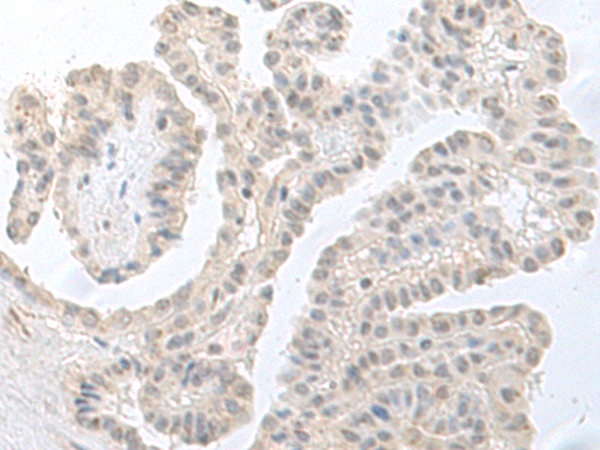

IHC positive control: |

Human esophagus cancer and Human thyroid cancer |

IHC Recommend dilution: |

40-200 |